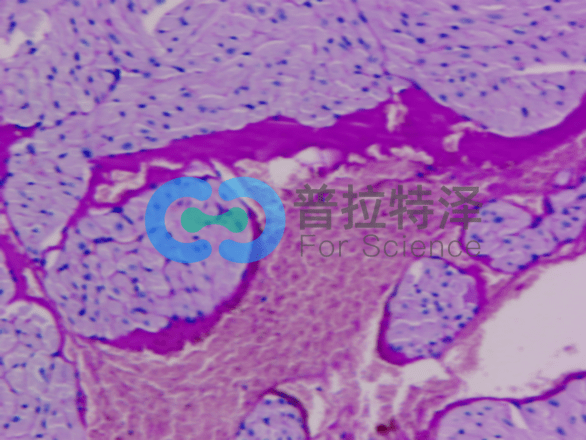

首先,我們來了解PAS染色的基本原理。它利用過碘酸將細胞中的多糖類物質(zhì)氧化,再通過雪夫試劑與氧化后的多糖結(jié)合,形成特征性的紅色或紫色沉淀。這種沉淀能夠清晰地顯示出細胞中的多糖類物質(zhì)分布和含量,從而幫助我們了解細胞的代謝狀態(tài)和功能特點。

在PAS染色實驗的第一個層次,我們需要關(guān)注實驗步驟和操作要點。實驗過程中,首先需要對樣本進行固定和脫水處理,以確保細胞的形態(tài)和結(jié)構(gòu)不受破壞。然后,利用過碘酸對細胞進行氧化處理,使多糖類物質(zhì)發(fā)生特定的化學(xué)變化。接著,通過雪夫試劑與氧化后的多糖結(jié)合,形成可見的沉淀。最后,通過顯微鏡觀察樣本的染色情況,分析細胞中的多糖類物質(zhì)分布和含量。

在第二個層次,我們將探討PAS染色實驗在細胞結(jié)構(gòu)與功能研究中的應(yīng)用。多糖類物質(zhì)在細胞中扮演著重要的角色,它們不僅是細胞壁和細胞膜的主要成分,還參與細胞的能量代謝和信號傳導(dǎo)等過程。因此,通過PAS染色實驗,我們可以觀察到細胞中多糖類物質(zhì)的分布情況,進而推斷出細胞的生理狀態(tài)和功能特點。這對于研究細胞的生長、分化和凋亡等過程具有重要意義,也為疾病的診斷和治療提供了重要的依據(jù)。

最后,在第三個層次,我們將思考PAS染色實驗的深層含義和引申價值。PAS染色實驗原理的應(yīng)用范圍廣泛,尤其在組織學(xué)研究領(lǐng)域發(fā)揮著不可替代的作用。通過PAS染色,我們可以觀察和分析不同組織類型中糖類的分布和變化,從而揭示其與組織功能、病理變化之間的關(guān)聯(lián)。例如,在糖尿病的研究中,PAS染色可以幫助我們觀察胰島細胞中糖原的積累情況,為糖尿病的發(fā)病機制和治療策略提供重要線索。此外,PAS染色還可用于研究腫瘤細胞的代謝特征、心血管疾病的病理變化等方面,為疾病的診斷和治療提供有力支持。

綜上所述,PAS染色實驗原理基于過碘酸的氧化作用和Schiff試劑的顯色反應(yīng),使得組織中的糖類物質(zhì)得以在顯微鏡下清晰呈現(xiàn)。這一原理在組織學(xué)研究中的應(yīng)用不僅豐富了我們對細胞結(jié)構(gòu)和功能的認識,還為疾病的診斷和治療提供了重要的實驗依據(jù)。普拉特澤生物誓帶大家透徹學(xué)習(xí)PAS染色實驗。當(dāng)然若果您有PAS染色實驗方法或其他醫(yī)學(xué)科研實驗外包的需求,歡迎隨時咨詢哦